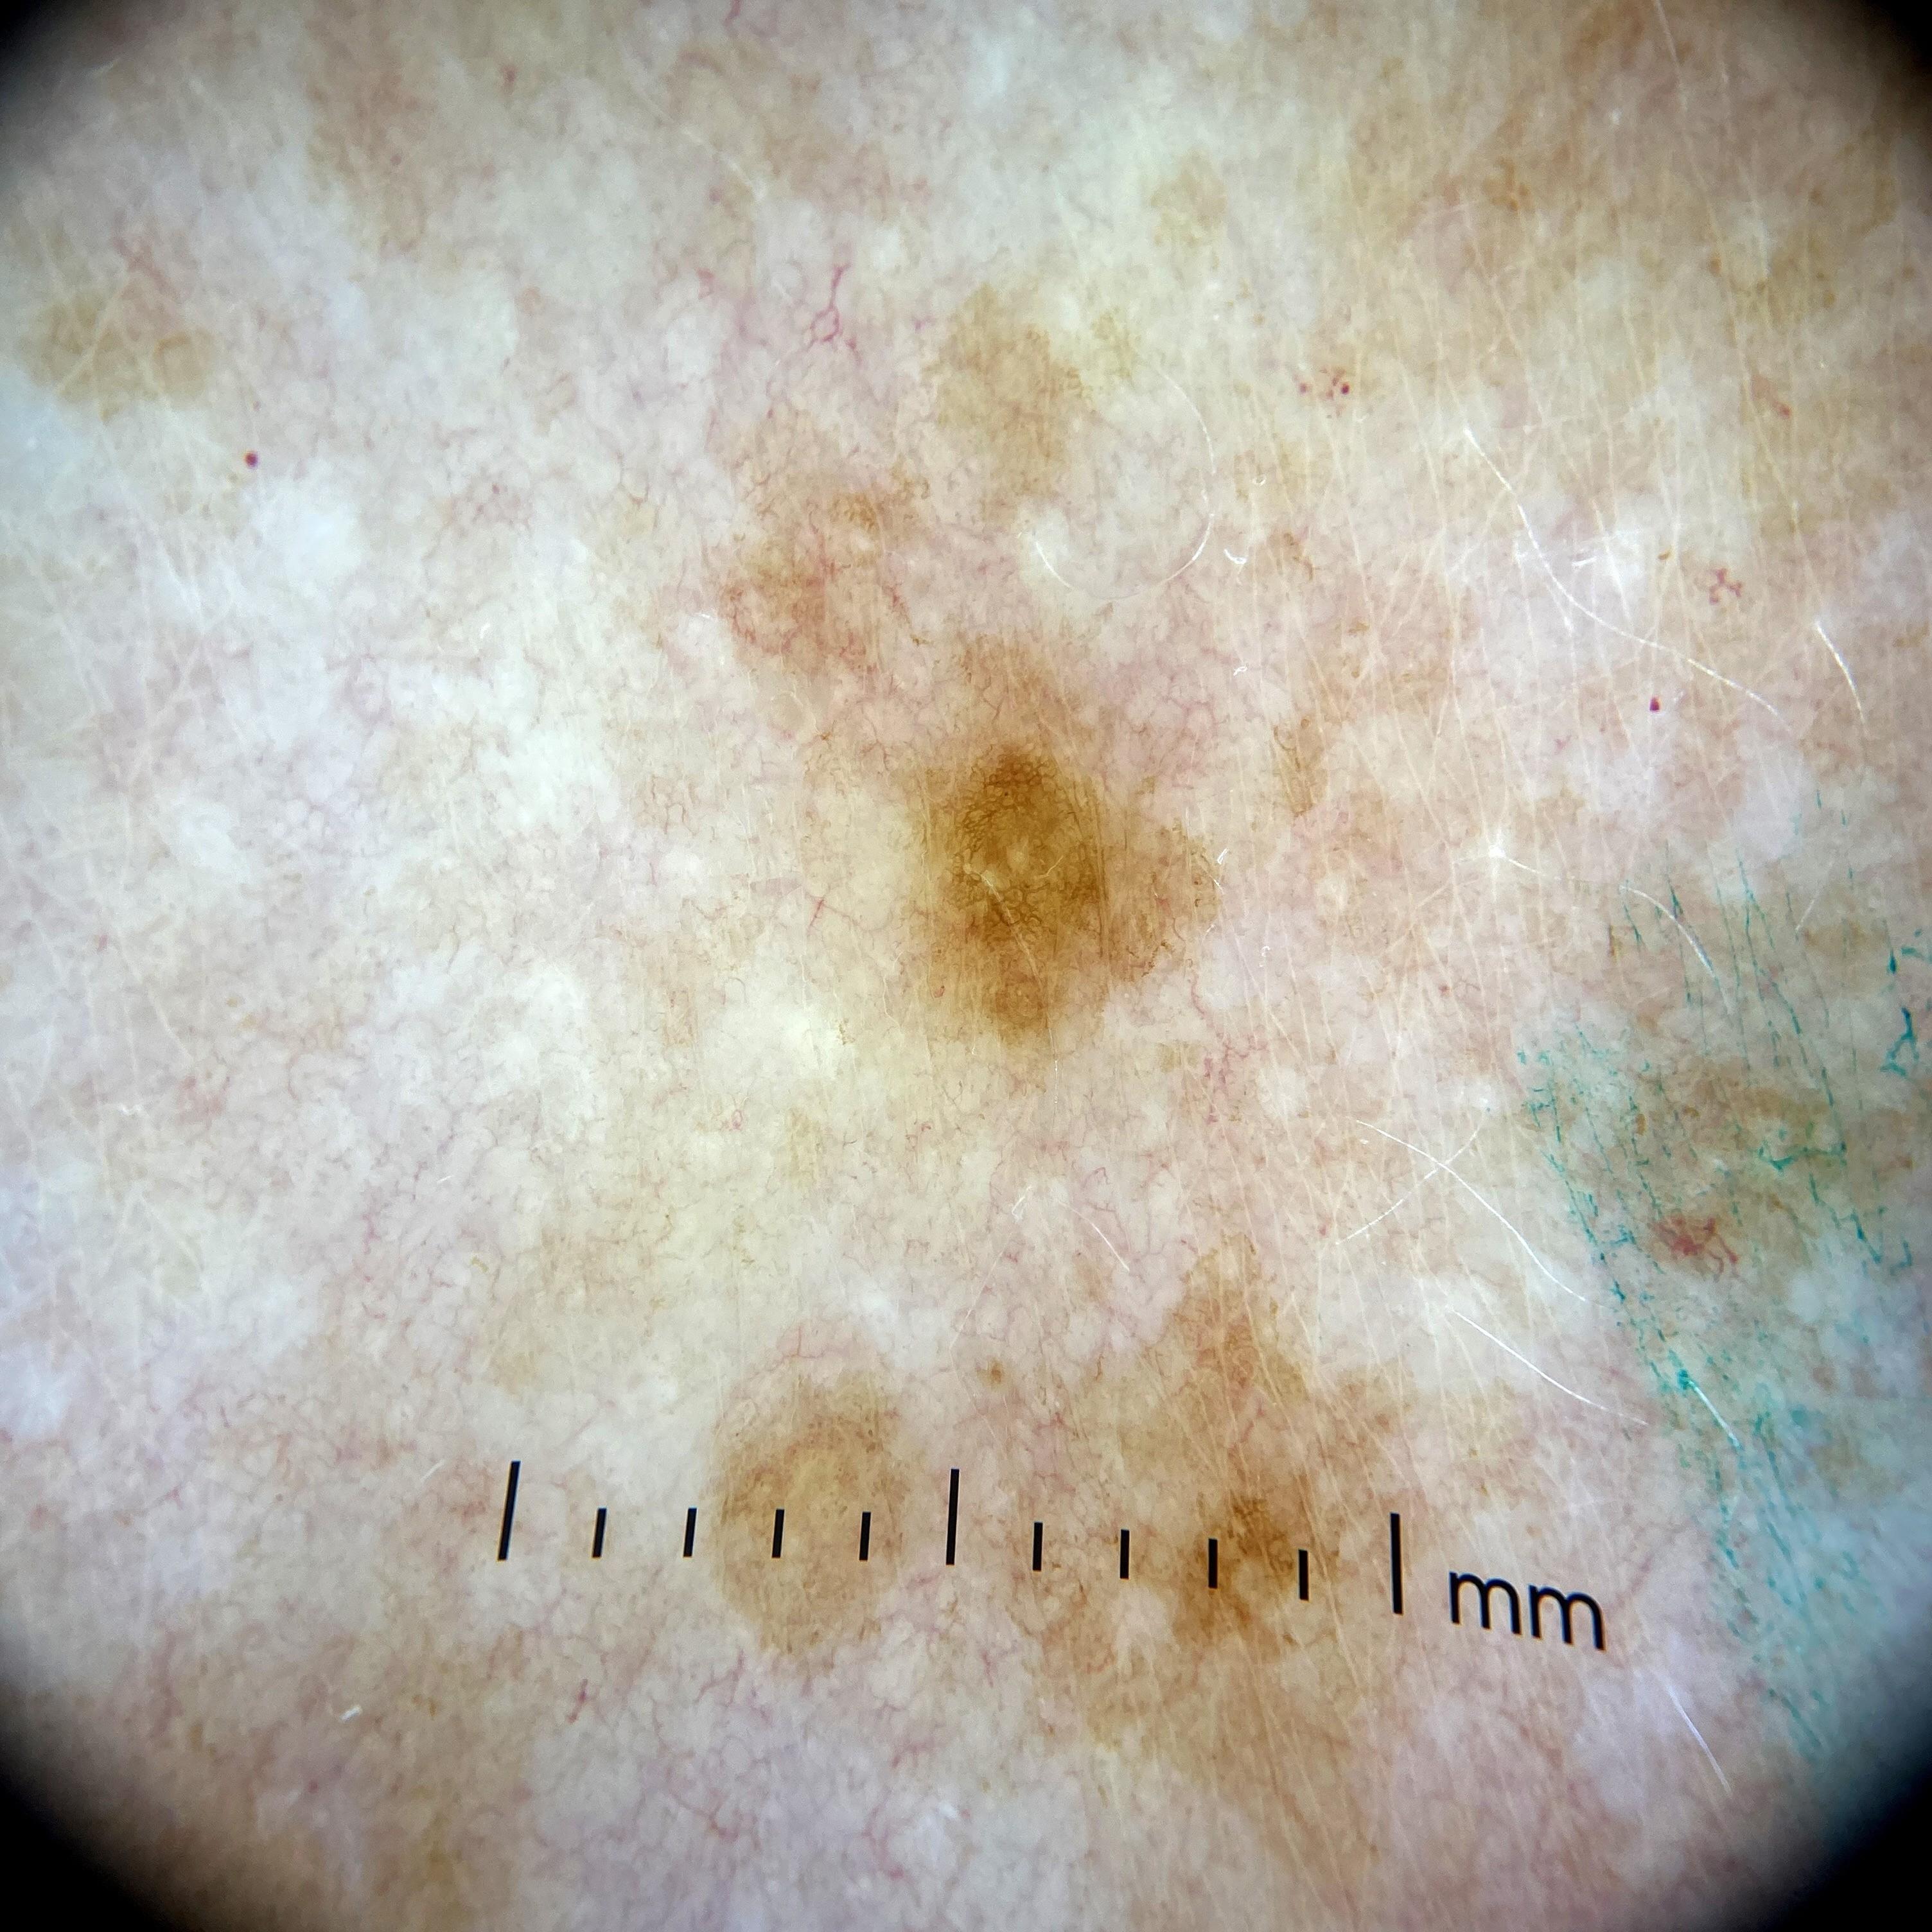

ISIC_0541590

Field Value

acquisition_day 335

age_approx 60

anatom_site_1 Upper extremity

anatom_site_general upper extremity

concomitant_biopsy False

diagnosis_1 Benign

diagnosis_confirm_type single image expert consensus

family_hx_mm True

image_manipulation instrument only

image_type dermoscopic

lesion_id IL_9840669

patient_id IP_1573786

personal_hx_mm True

sex female